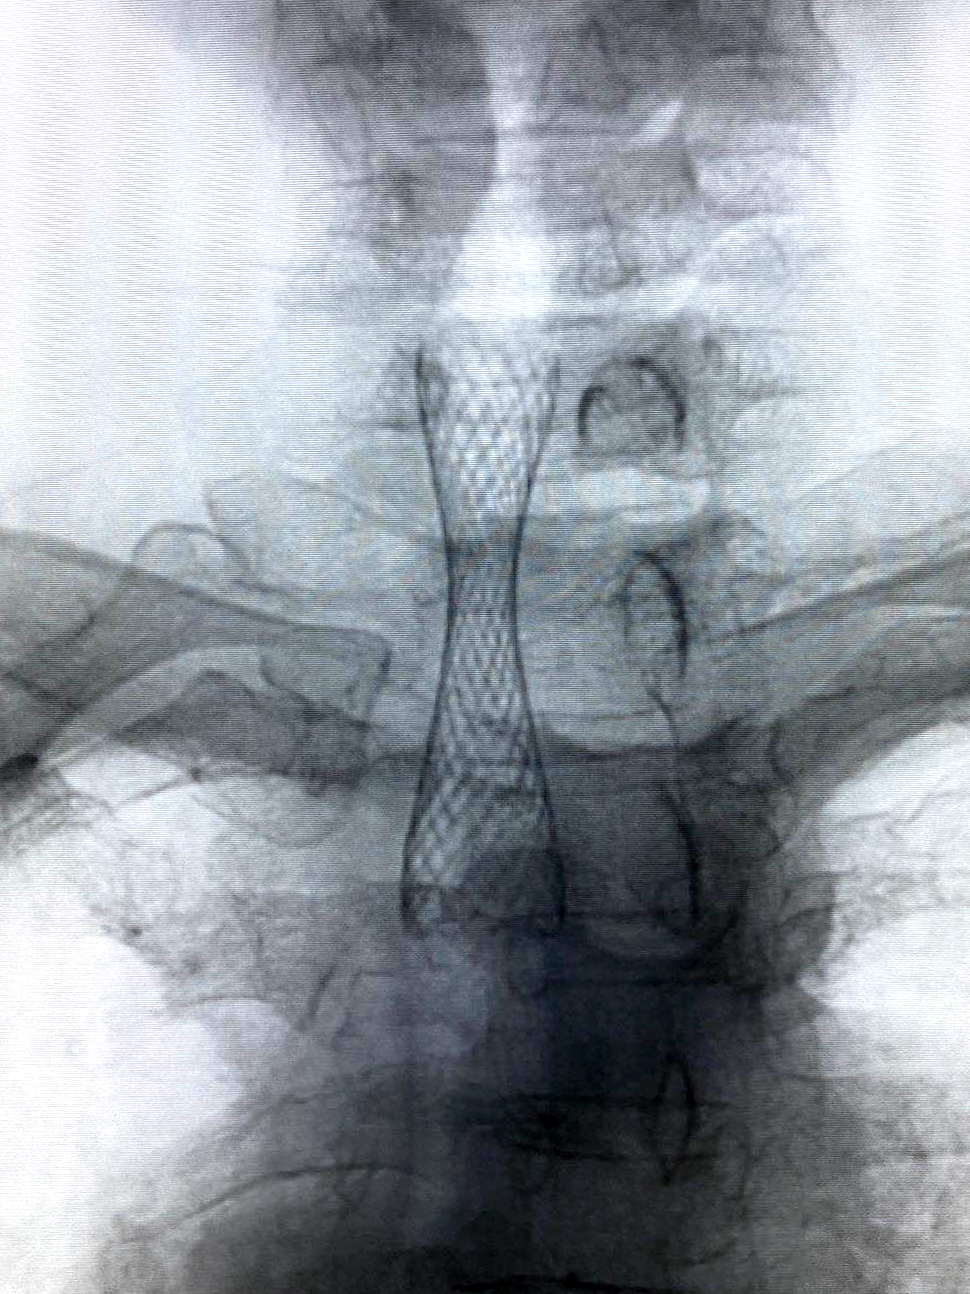

但這些問題統(tǒng)統(tǒng)難不倒我們經(jīng)驗(yàn)豐富、身經(jīng)百戰(zhàn)的放射科介入團(tuán)隊(duì)。局麻下,他們通過導(dǎo)管將導(dǎo)絲順利插入氣管,再順沿導(dǎo)絲置入氣管支架套裝,準(zhǔn)確定位后快速釋放支架,全程僅用時(shí)3分鐘。支架完全打開,將只有一線生機(jī)的氣管牢牢撐開,吹風(fēng)樣的呼吸聲完全消失,患者瞬間恢復(fù)正常呼吸,效果立竿見影。